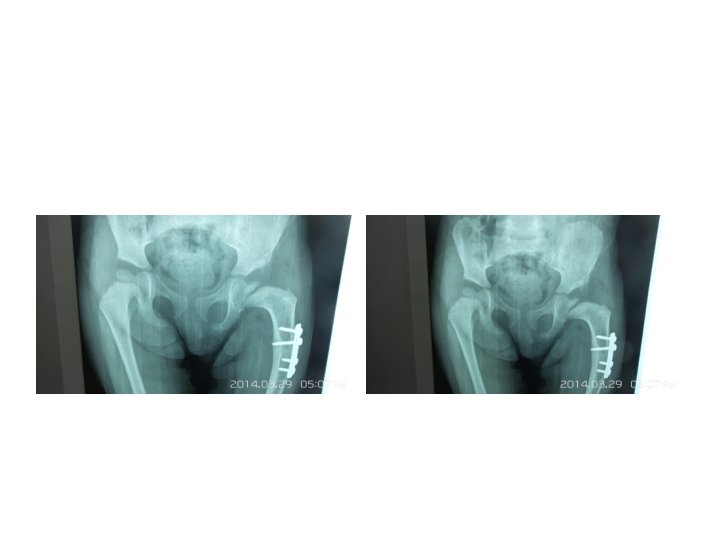

Somerville technique of anterior open reduction in congenital dislocation of hip. A, Bikini incision.

Somerville technique of anterior open reduction in congenital dislocation of hip. A, Bikini incision. B, Division of sartorius and rectus femoris tendons and iliac epiphysis. C, T-shaped incision of capsule. D, Capsulotomy of hip and use of ligamentum teres to find true acetabulum. E, Radial incisions in acetabular labrum and removal of all pulvinar from depth of true acetabulum. F, Reduction and capsulorrhaphy after excision of redundant capsule. G, Developmental dislocation of right hip. H, After anterolateral open reduction. I, At age 7 years; note remodeling of femoral head and acetabulum.